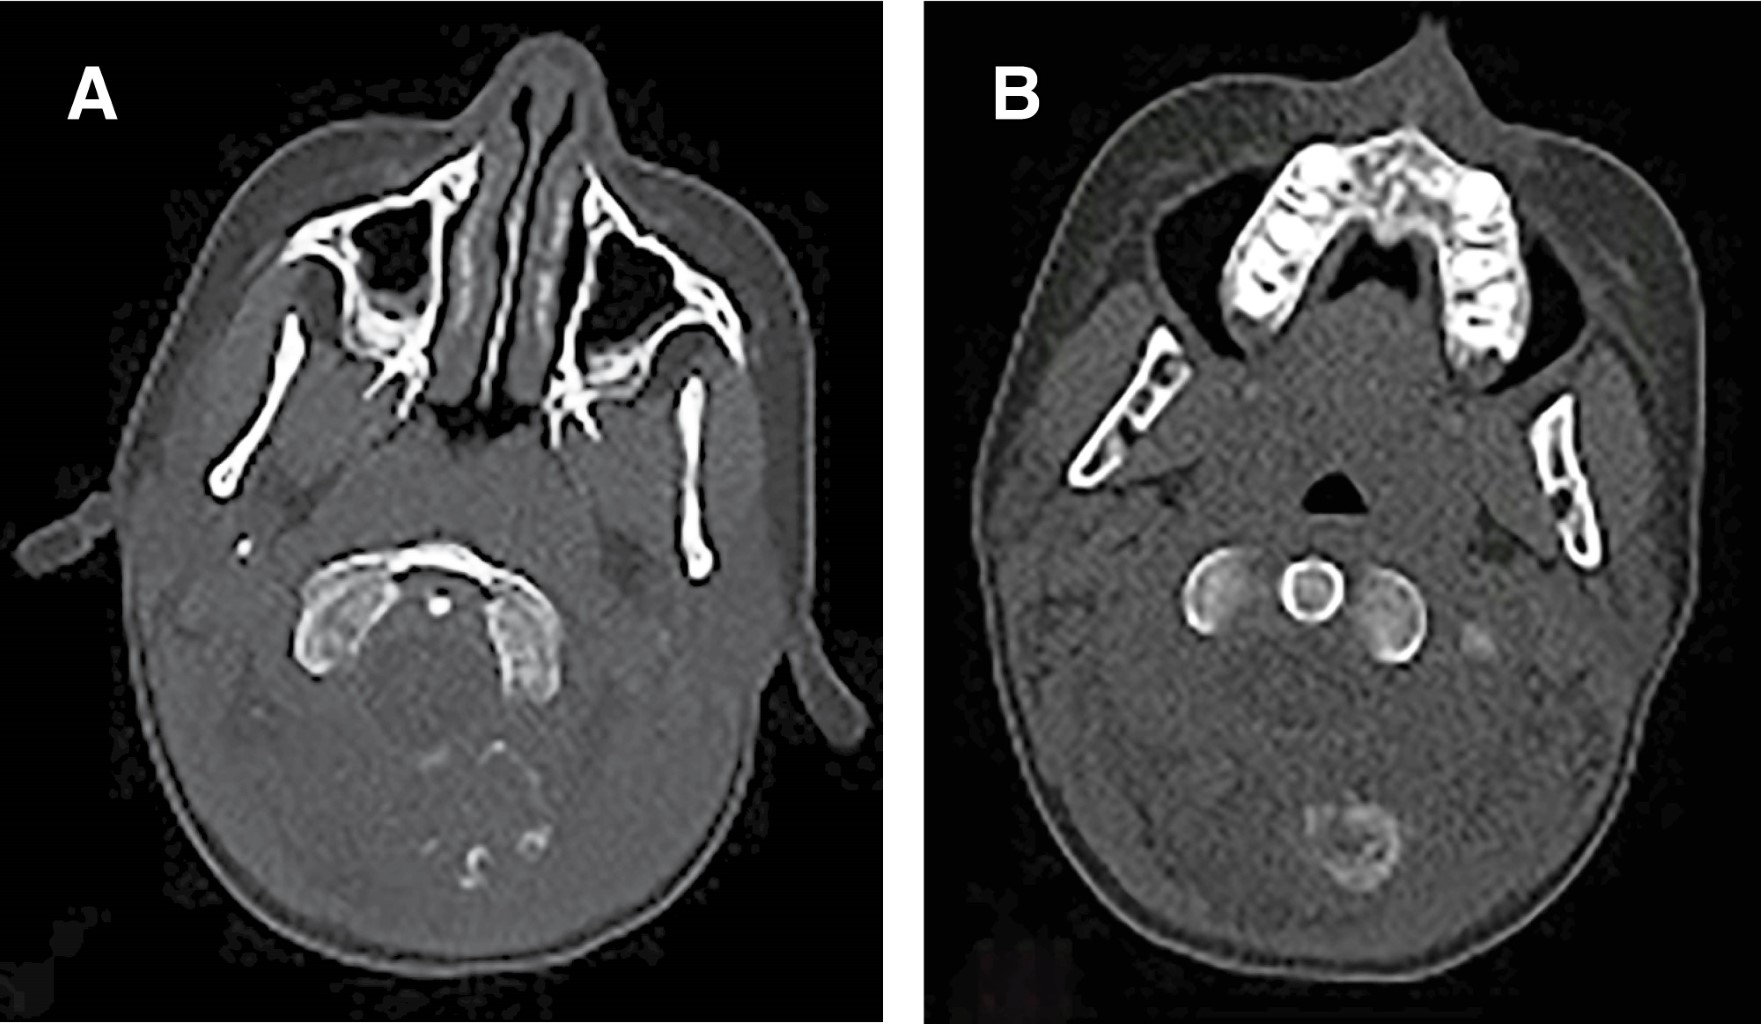

Introduction: myositis ossificans (MO) is described as a non-neoplasic heterotopic bone formation at soft tissues and muscle. It is a rare entity in children, but it must be included within the differential diagnosis of a malignant tumor or an infection. Material and methods: the objective of this retrospective study is to describe three clinical cases of circumscribed myositis ossificans; the first one is a 10-year-old girl with a post-traumatic cervical injury, the second one is an 11-year-old boy with an atraumatic-type distal thigh injury, and the third one is an 8-year-old boy with a post-traumatic right thigh tumor. Results: the diagnosis was made on the basis of the clinical presentation, radiologic imaging and histopathological findings. The results obtained by conservative treatment were good in all cases, with resolution of pain and progressive reduction in size of lesions, without registering complications during follow-up. Conclusion: myositis ossificans is a rare entity, whose diagnosis is usually complex and may require a multidisciplinary team, and whose prognosis is nevertheless favorable.

Figure 4